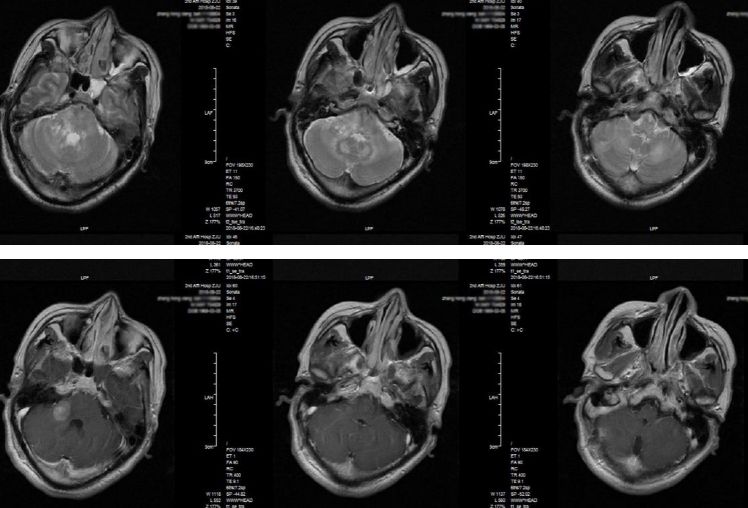

复查头部增强磁共振显示病灶较前有增大(图3)。胸部CT检查提示肺部感染合并少量胸腔积液(图4)

图3. 复查头部增强磁共振,提示右侧桥臂及左小脑病变较前增大。